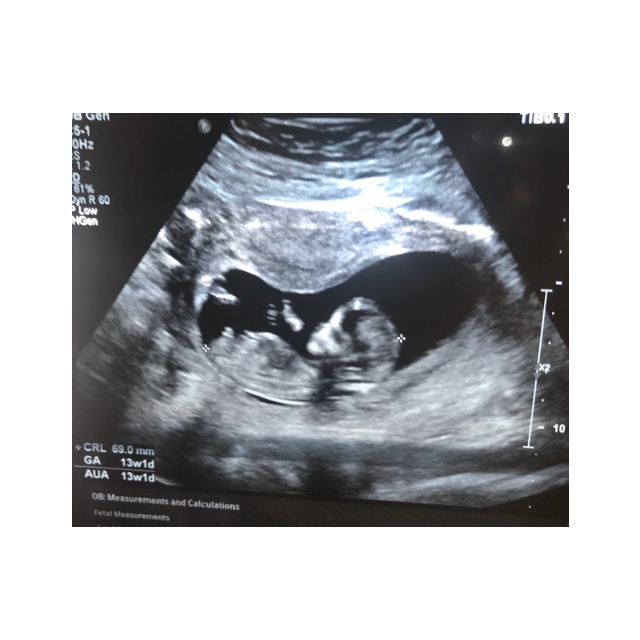

I just had my 12 week scan yesterday. I was 12 weeks 4 days but baby was measuring 13 weeks 1 day.

I didn’t get many good photos & I’m not even sure if the nub is pictured. I’d love any guesses that you might have![]()

Is this even a nub? 12weeks 4days

The baby is very curled up and I feel like we're not seeing the entire nub here, plus it's earlier than I like to guess. I just can't get a good feel on these, darling baby though!